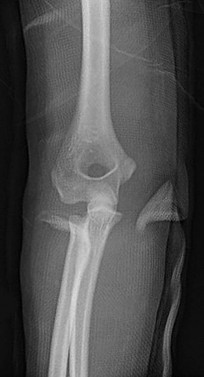

Question 11:

A 14-year-old female presents for operative evaluation of adolescent idiopathic scoliosis. Standing full-length spine radiographs show a main thoracic curve of 55 degrees and a lumbar curve of 35 degrees. The proximal thoracic curve is 20 degrees. On side-bending radiographs, the main thoracic curve corrects to 30 degrees, the lumbar curve corrects to 15 degrees, and the proximal thoracic curve corrects to 5 degrees. Based on the Lenke classification, what is the correct curve type?

Explanation:

In the Lenke classification system, a curve is considered structural if it fails to correct to < 25 degrees on side-bending radiographs or has an associated regional kyphosis > +20 degrees. Here, the lumbar curve corrects to 15 degrees (non-structural) and the proximal thoracic corrects to 5 degrees (non-structural). The main thoracic curve is the major curve (largest magnitude, 55 degrees). A major main thoracic curve with non-structural minor curves is classified as a Lenke Type 1.